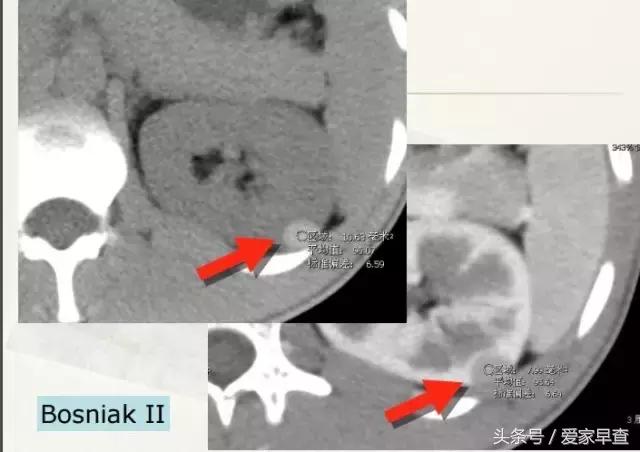

这张片子上这两个囊肿虽然也叫囊肿,但是它跟刚才那张片子上的那种不太一样的。你这个囊肿看到箭头所示是有一些分隔,还有一个稍微厚点儿的壁。但是它又不那么大,那我们就把它划成BosniakⅡ。BosniakⅡ的恶性可能性有多少呢?是小于0.5%,几乎是不太可能是恶性的,如果它最终变成恶性,就跟中彩票差不多。这种当它也不太大的时候,也是不需要处理的。